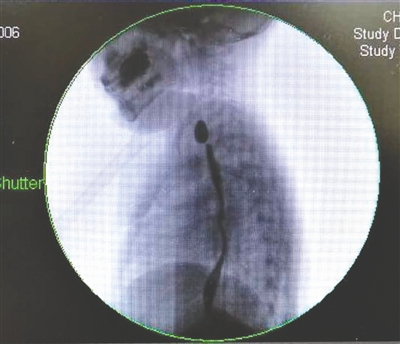

李勇刚介绍,彤彤到儿童医院接受治疗后,医院对其进行了3次食道扩张手术,但每次扩张后仅几天便出现收缩,效果不佳。9月12日,医院为彤彤实施了食道支架置入手术,在她的食道内置入了全覆膜食管支架,使得食管腔明显增大。如顺利,6个月后,该支架将取出。

2016年,美国两岁男童Logan Stiff在托儿所误吞下一块遥控器中的纽扣电池(左图),电池烧穿他的食道,影响气管膜壁,导致Stiff可能失去发声能力。当时Stiff出现了未知原因的呕吐症状,Stiff的父母迅速把他送去了医院。